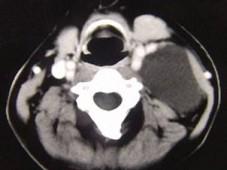

问题 男性,40岁,颈部出现无痛性囊性包块2年余,CT扫描如图所示,最可能诊断为 ( )

选项 A、神经源性肿瘤 B、颈动脉鞘瘤 C、血管瘤 D、淋巴结肿大 E、淋巴管瘤

答案 E